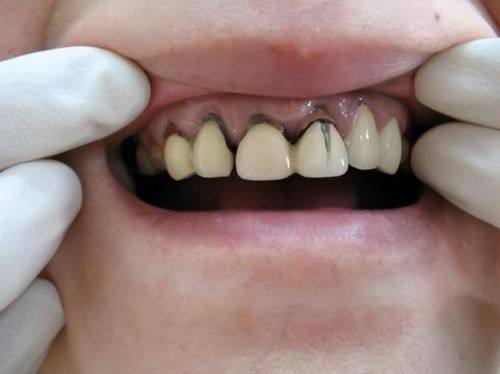

3. 口腔美容修复:如冷光美白、美加瓷贴面修复等,医生在这些领域拥有大量治疗经验及病例。

1. 常笑:矫正及美容修复主诊医师,擅长冷光美白、隐形矫正、青少年口腔综合诊疗、金属自锁托槽、牙齿早期矫治,在美加瓷贴面修复及数字化矫正有大量治疗经验及病例。

2. 章蓉:拥有近二十年口腔临床经验,在口腔种植修复,牙齿美白及牙齿残根残冠的保留修复等方面有较深的造诣,擅长微创种植牙、微创即刻种植、微痛种植牙、全口/半口牙颌种植、牙贴面。